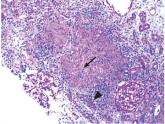

ArticleWeight loss, fatigue, and renal failureAuthor:Qiwei Paulson, MDPublish date: August 1, 2017A 37-year-old man has gradually lost 100 lb over the past 2 years, with progressive fatigue and malaise.Read More